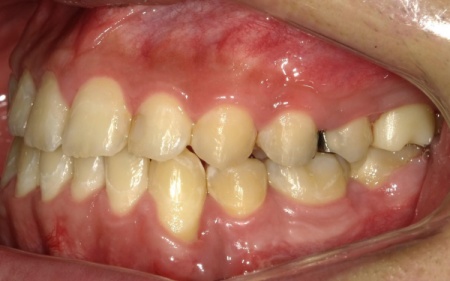

10代男性 顎変形症が原因で下顎がずれて非対称になっていた噛み合わせをサージェリーファースト法を併用した矯正治療で改善した症例

拝見したところ、骨格の問題により下前歯が上前歯より前に出ている前歯部反対咬合と、前歯が開いて噛み合わないオープンバイトが認められました。

さらに、下顎の骨が右方向にずれて上下の歯が噛み合う面が斜めになっていることで、顔面の非対称も見られます。

まずは、歯を正しい位置に動かすスペースを確保するために、左下奥歯(第1小臼歯)を抜きました。続いて、サージェリーファースト法による下顎骨骨切り手術を慎重に行います。

次に、上下の歯にマルチブラケット装置を装着し、歯を動かす起点とするためにアンカースクリューを埋入します。

今回は患者様と相談のうえ、治療中の審美性を考慮して目立ちにくい色調のブラケットを採用しました。

その後は定期的に来院いただき、ワイヤーの調整を行いながら歯並びと噛み合わせを徐々に整えていきました。

矯正治療が終了したあとは、以前神経を除去する処置をしたものの被せ物を装着していなかった左上奥歯に対し、強度と審美性を兼ね備えた白い素材のジルコニアクラウンを装着する治療を行っています。

最後に、審美性、噛み合わせ、機能性などに問題がないことを確認し、治療を終了しました。